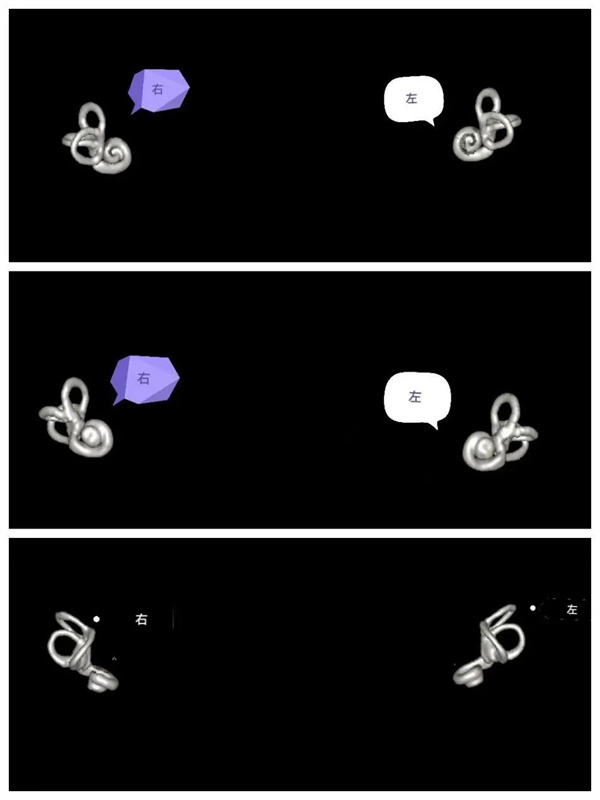

圖6:MIP圖,完美顯示雙側(cè)內(nèi)耳解剖輪廓。

圖7:VR圖,雙側(cè)內(nèi)耳解剖輪廓圖的不同角度顯示圖(后面觀,前面觀,上面觀)。